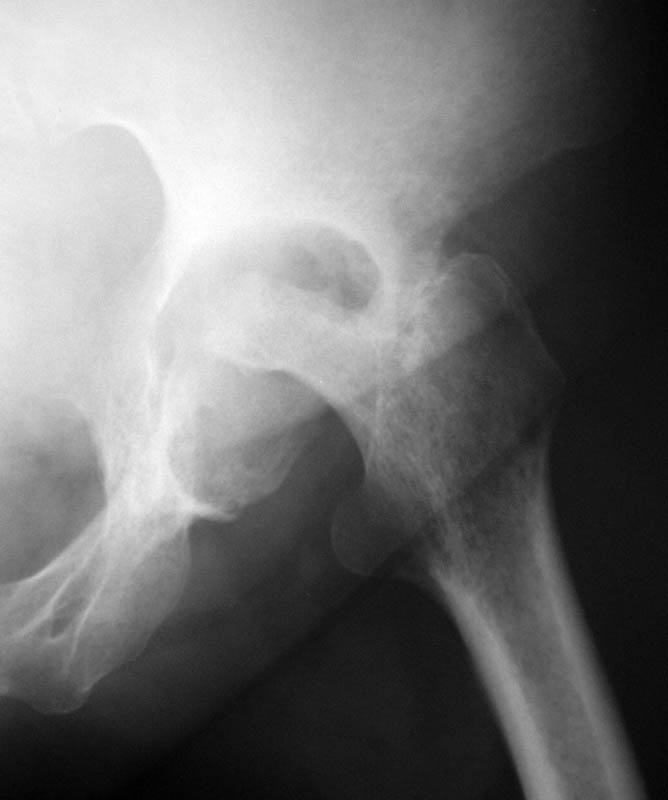

Последствия коксита

Женщина, 45 лет. В марте перенесла левосторонний коксит неизвестной этиологии. Специфику и онкологию исключили.

Интраартикулярных инъекций не было. Сейчас процесс клинически и рентгенологически - стабилизировался. Состояние вполне удовлетворительное.Предполагается тотальное эндопротезирование с пластикой полости аутокостью. Возможна ли бесцементная <чашка>? Заранее благодарю! С уважением,А.В.Владзимирский

Пртезирование через пол года после коксита закончившегося лизисом сустава, который на снимках выглядит как гнойный? Что значит неизвестной этиологии?

Уважаемый коллега! Последняя версия - мы пролистали ренгенологическую книженцию-так картинка вполне подходит под сустав Шарко (neuropatic joint ). В тазобедренном суставе патология редкая (но меткая). Ищите причину - варианты - нейросифилис, сирингомиелия, опухи спинного мозга (и выше тоже) компрессия спинного

мозга извне, рассеяный склероз, алкоголизм. А так-же : склеродерма ,Рейно,ревматоидный артрит, амилоидная инфильтрация нервов,и это не считая всяких менингеомиелоцеле,asymbolia,Riley-Day syndrom,и все возможные другие нейропатии. На данном этапе не спешите оперировать(протезирование протиопоказано при нейропатических суставах),проконсультируйтесь с классным невропатологом,сделайте МЯР головного озга и

весь позвоночник. И держите нас в курсе - случай крайне интересный :)